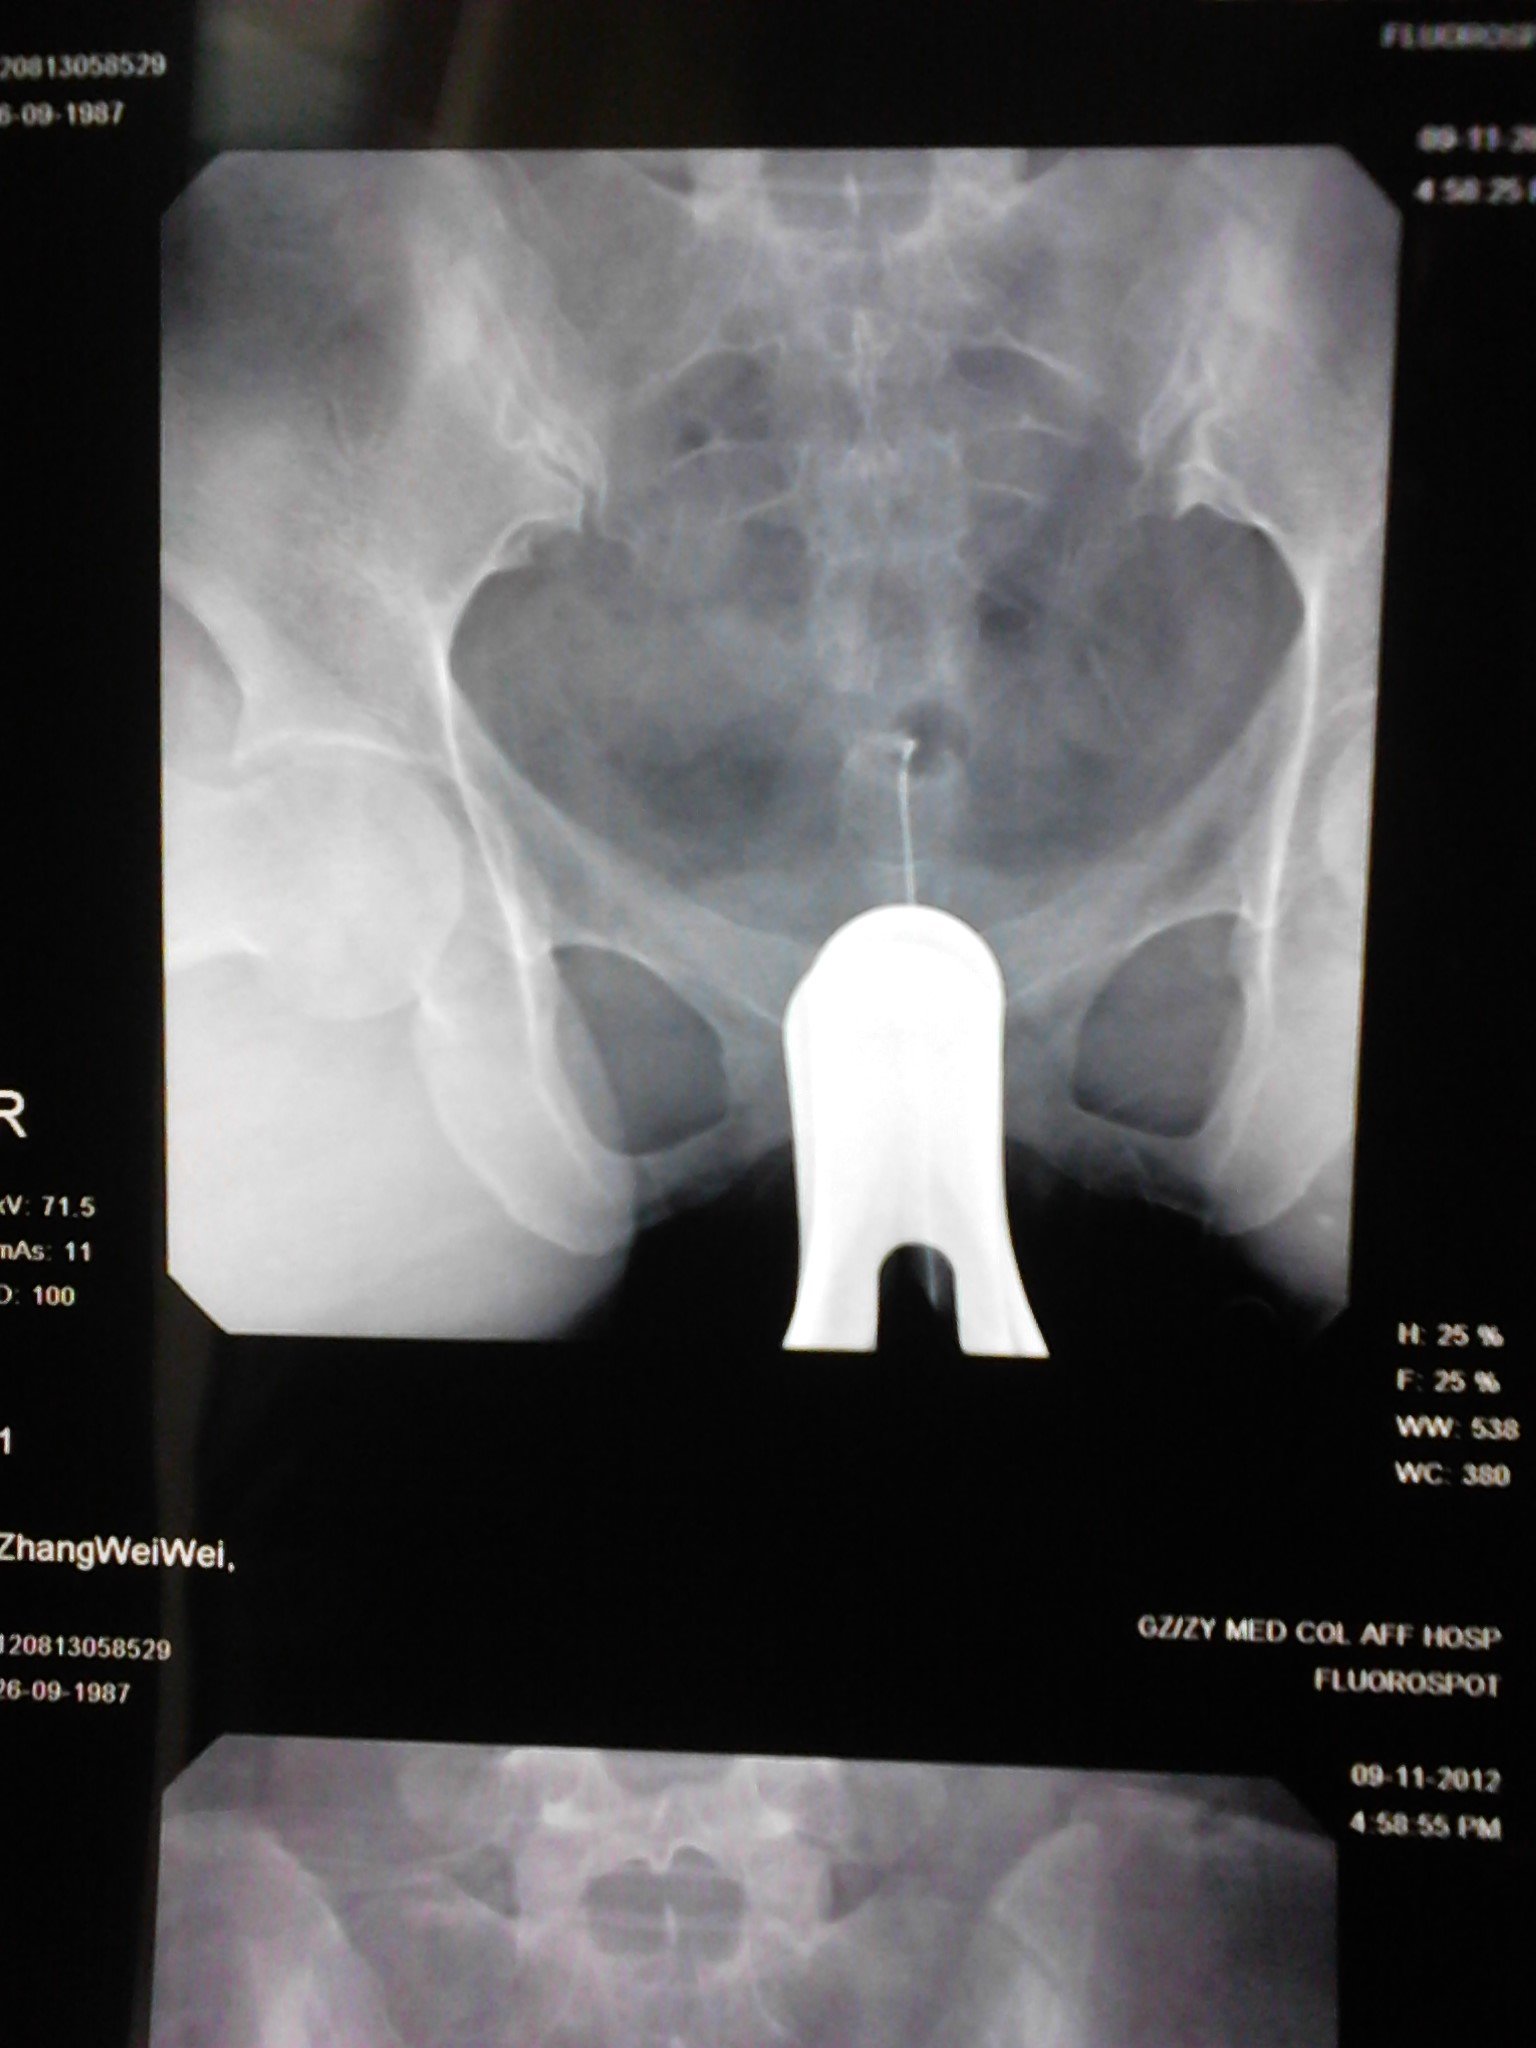

请大家看看造影的报告单,,,还有怀孕的机会吗? 患者信息:女 25岁 贵州 遵义 病情描述(发病时间、主要症状等):子宫腔大小.形态无明显异常.子宫粘膜面光滑整齐.宫腔内见气囊及气泡所致充盈缺损。双侧输卵管全程显影.双壶腹部粘膜皱襞增粗.双侧伞端呈锥状.其内造影剂呈喷射状进入腹腔.进入腹腔之造影剂弥散欠佳曾经治疗情况及是否有过敏、 遗传病 史:现在正在吃中药 点击展开 宇文令秋_1EAj 2012-06-17 13:32 满意回答 帮顶。。。。。。。。。。。。 欧阳弘新_SmTk 2012-06-17 13:51 宝宝知道提示您:回答为网友贡献,仅供参考。 相关问题 医生看看我的造影报告单 数字化X造影检查报告单还能生育吗? 做完造影这样的结果,次月跟第三个月会怀孕吗

患者信息:女 25岁 贵州 遵义 病情描述(发病时间、主要症状等):子宫腔大小.形态无明显异常.子宫粘膜面光滑整齐.宫腔内见气囊及气泡所致充盈缺损。双侧输卵管全程显影.双壶腹部粘膜皱襞增粗.双侧伞端呈锥状.其内造影剂呈喷射状进入腹腔.进入腹腔之造影剂弥散欠佳曾经治疗情况及是否有过敏、 遗传病 史:现在正在吃中药